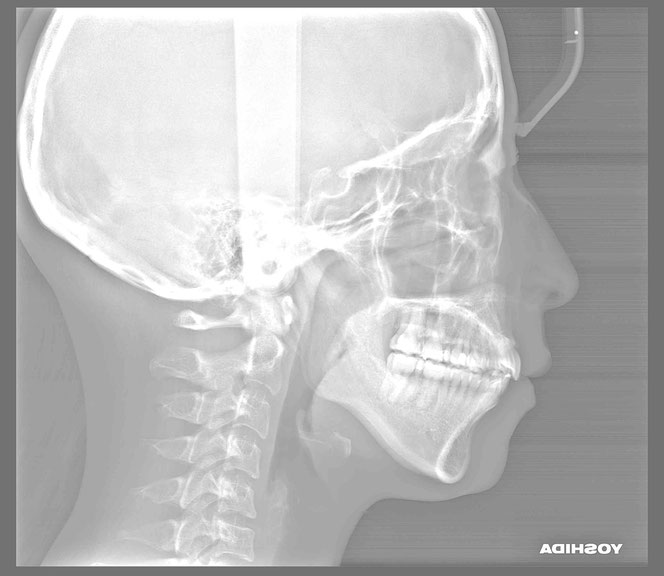

治療後の変化

再生治療により、

2~3ミリ下がっていた歯ぐきが回復。

歯の長さが自然なバランスに戻り、

厚みのある丈夫な歯ぐきが再建されました。